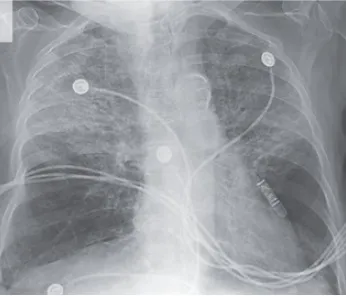

Cómo tratar la fibrilación auricular en la enfermedad renal crónica

Cómo tratar la fibrilación auricular en la enfermedad renal crónica

El paciente con ERC (Enfermedad Renal Crónica) tiene una alta prevalencia de fibrilación auricular. ¡Consulta esta actualización sobre su manejo!